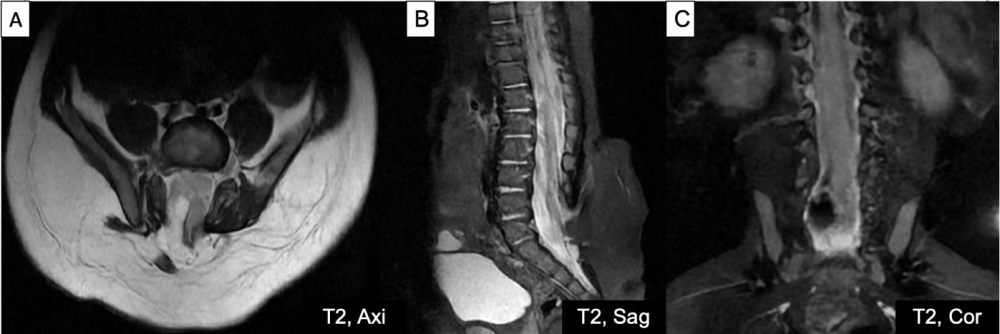

Hình 2. Cộng hưởng từ cột sống thắt lưng chuỗi xung T2 trên mặt phẳng cắt ngang, đứng dọc, đứng ngang (A-C) với khuyết cung sau các đốt sống cùng S1-S3, kèm túi thoát vị màng tủy chứa mô mỡ liên tục với mỡ dưới da, bên trong chứa mỡ và một phần tủy sống; đường kính cổ túi thoát vị #20mm, chóp tủy nằm thấp ngang mức S1.